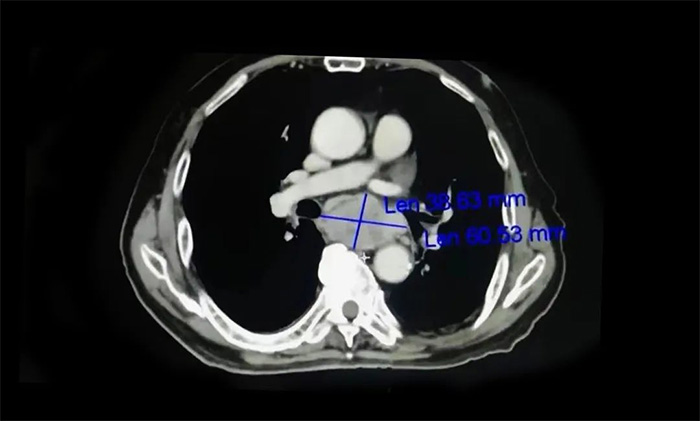

需要提醒的是,食道癌早期患者在就醫時常主訴“嗓子處有東西”,這和臨牀上常見的咽炎症狀相似,兩者需進行鑑別,要根據患者病史、症狀、體徵、食管鏡檢查、影像學檢查結果等進行綜合判斷。其中,食管鏡檢查加活檢病理檢查對診斷是否患有食管癌具有重要意義,影像學檢查則可為評估腫瘤分期提供可靠的依據。

▲ 影像學檢查為評估食管癌分期提供依據